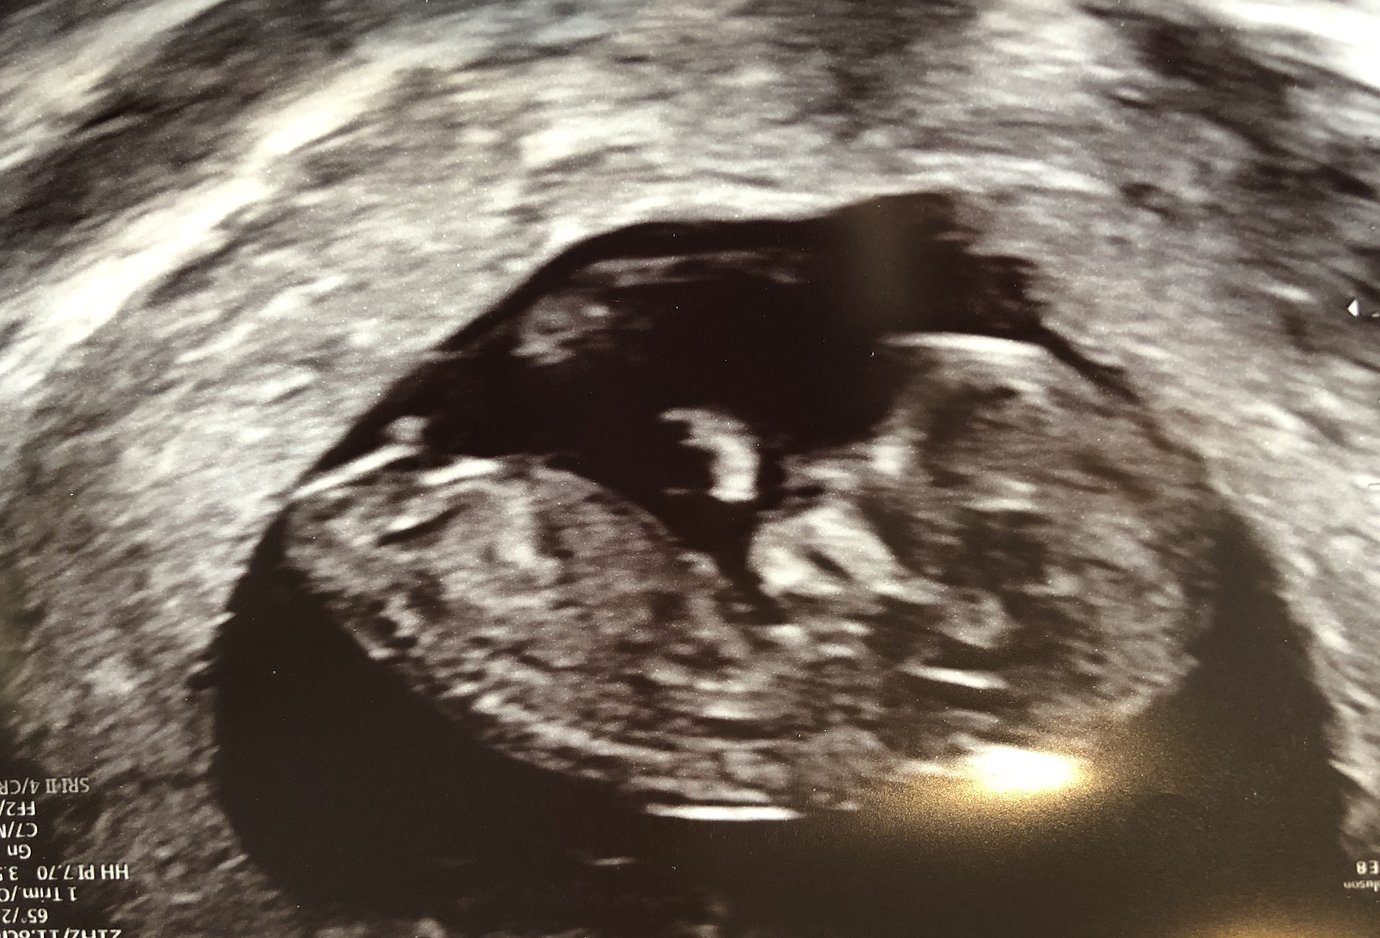

Have also included my 16 week scan pic just in case! Attachment 41945Attachment 41946Attachment 41947

Then I looked at the last pic again. I leant towards boy then.

I can't see a nub sorry